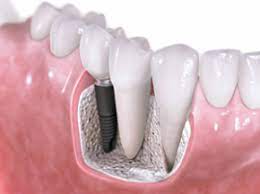

임플란트는 턱뼈에 임플란트 자체를 묻는 치료입니다. 특히 하악의 뼈 중에는 굵은 신경과 혈관이 지나가는 하치조관이 존재하는데 하치조관의 신경을 만지면 신경이 손상되거나 끊어질 수 있습니다.

임플란트 자체로 충치나 치주병이 발생하지는 않습니다. 그러나 치주병과 유사한 임플란트 주번염에 걸릴 수 있습니다.

임플란트 주변염에 걸리면 임플란트 주위의 잇몸이 부어오르거나, 임플란트를 지지하고 있는 치조골이 녹아 버리기 때문에, 최악의 경우는 임플란트를 제거해야 됩니다.